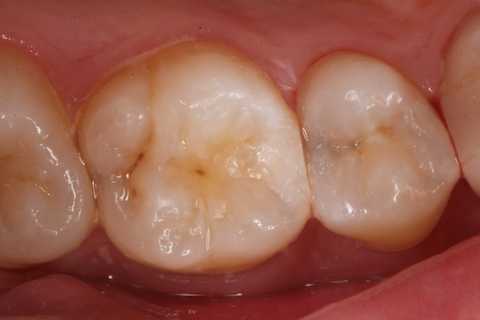

20代女性、右上6、咬合性外傷による隣接面カリエス

クラックが気になるのだが、象牙質には広がっていないようだったので、このまま充填した。

では時系列でどうぞ